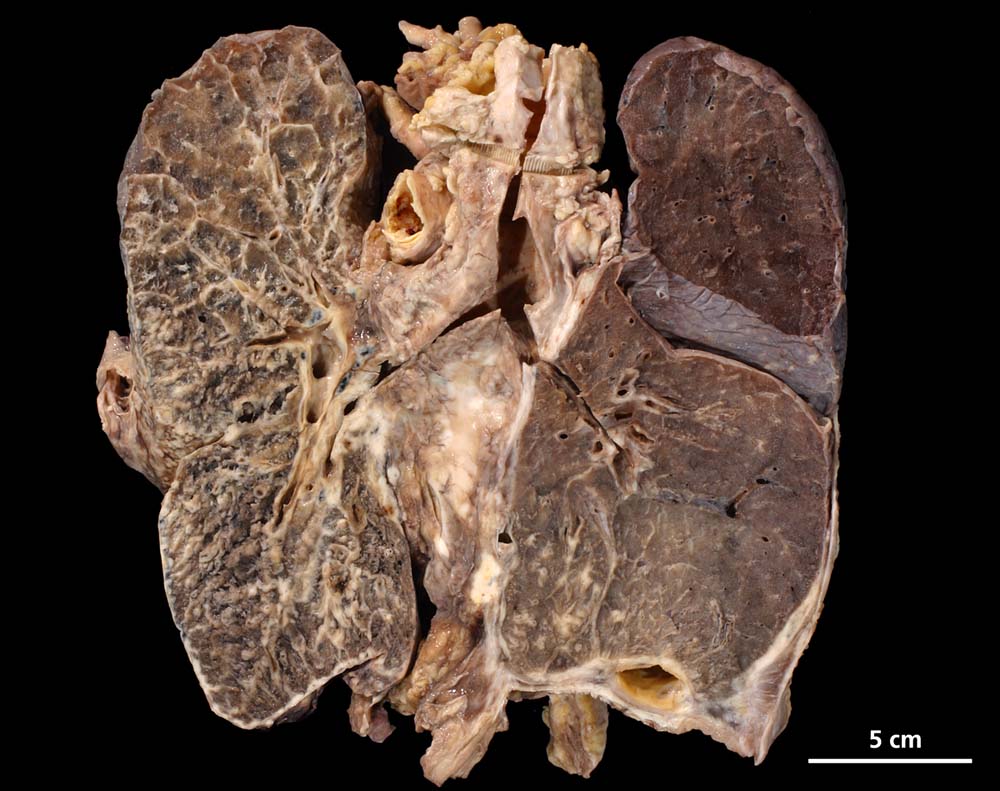

Das metastatische Wachstumsmuster von primären Bronchuskarzinomen und extrapulmonalen Tumoren innerhalb der Lunge ist variabel. Hämatogene Metastasen imponieren makroskopisch als multiple scharf begrenzte rundliche Knoten in allen Lappen meist in peripherer Lage. Der metastatische Befall von Lymphknoten kann durch direkte Tumorinfiltration durch den Primärtumor erfolgen (=per continuitatem) oder über die Lymphgefässe. Bei einer ausgeprägten lymphogenen Tumorausbreitung erscheinen subpleurale mit Tumor gefüllte Lymphgefässe makroskopisch als prominente weisse Streifen. Mikroskopisch lassen sich Tumorinfiltrate in peribronchialen und perivaskulären Lymphgefässen nachweisen (=Lymphangiosis carcinomatosa). Hepatozelluläre Karzinome metastasieren typischerweise in Form von Tumorembolien (> 1279) hämatogen in die Lunge.

• Sternförmiges Karzinom mit zentraler Vernarbung mit reichlich schwarzem Anthrakosepigment.

• Peritumorales Lungenemphysem (Traktionsemphysem).